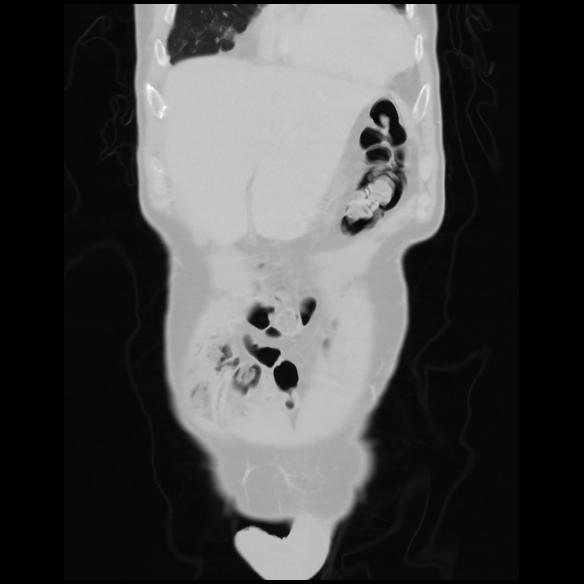

6 CUERPO,CE,Coronal,3.000,CUERPO,Coronal,